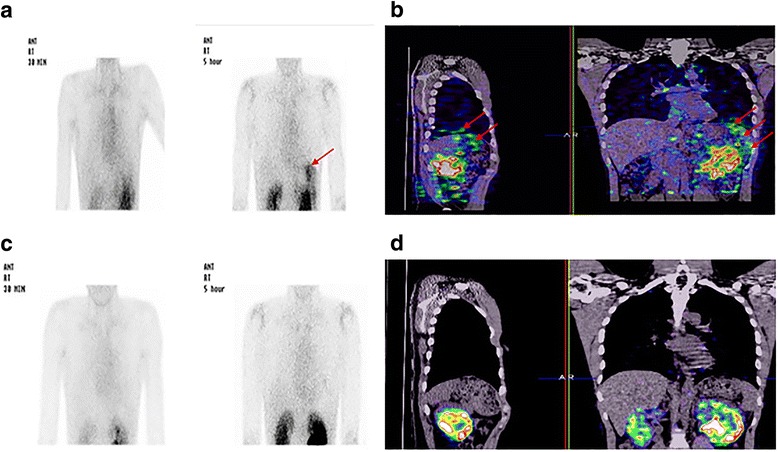

An enhanced CT scan on day 6 after admission revealed diffuse left renal swelling and fluid collection in the anterior pararenal space. No specific urine leakage was seen on intravenous pyelography. There was no distal obstruction on these studies. Under suspicion of urinothorax, a 99mTc DTPA (diethylenetriaminepentacetate) renal scan was performed on day 12 after admission. Radionuclide scintigraphy and single-photon emission computed tomography (SPECT-CT) using 99mTc DTPA revealed urine leakage from the lower pole of the left kidney to the left sub-diaphragm and the pleural space 5 h after injecting the tracer (Fig. 2). This leakage was also confirmed through retrograde pyelography (RGP) (Additional file 1: Fig. S1). A double-J stent and Foley catheter were inserted for 4 weeks to reduce leakage pressure and he was tolerable with this intervention. Follow-up radionuclide scintigraphy and SPECT-CT did not show any kidney or tracer leakage at the sub-diaphragm or pleural space (Fig. 2). The pigtail catheter was removed with full lung expansion, and the double-J stent and Foley catheter were taken out safely. He is being followed in our outpatient department with no recurrence of urinothorax for 1 year.

Fig. 2.

a Initial 99mTc DTPA: Not 30 min, but 5 h posterior static image showing significant buildup of trace in the left sub-diaphragm and pleural space (arrow). b Initial SPECT-CT: Not 30 min, but 5 h scanning image demonstrating tracer uptake in the right sub-diaphragm and pleural space (arrow). c Follow up 99mTc DTPA: 5 h posterior static image showing complete disappearance of buildup of trace in the right sub-diaphragm and pleural space. d Follow up SPECT-CT: 5 h scanning image demonstrating disappearance of tracer uptake in the right sub-diaphragm and pleural space

Urine can reach the pleural space from the retroperitoneal space via lymphatic drainage [3, 5, 6] or with direct movement of the abdominal fluid into the pleural space through anatomical defects in the diaphragm, which is the dominant mechanism for a hydrothorax in patients with cirrhosis and ascites [3, 5–7]. The rapid accumulation of pleural fluid, which is common in patients with urinothorax, demonstrates that the latter may have been the dominant mechanism in our patient. The radionuclide scintigraphy and SPECT-CT scan performed using 99mTc DTPA showed that high amounts of tracer were linked between the kidney, the left sub-diaphragm, and the left thorax 5 h after injecting the tracer. This suggests that the urinothorax mechanism may be due to direct movement from the retroperitoneum to the pleural cavity via a diaphragmatic defect. SPECT-CT was a good diagnostic tool to show the tracer flow two-dimensionally. No previous study has demonstrated urinothorax using SPECT-CT.